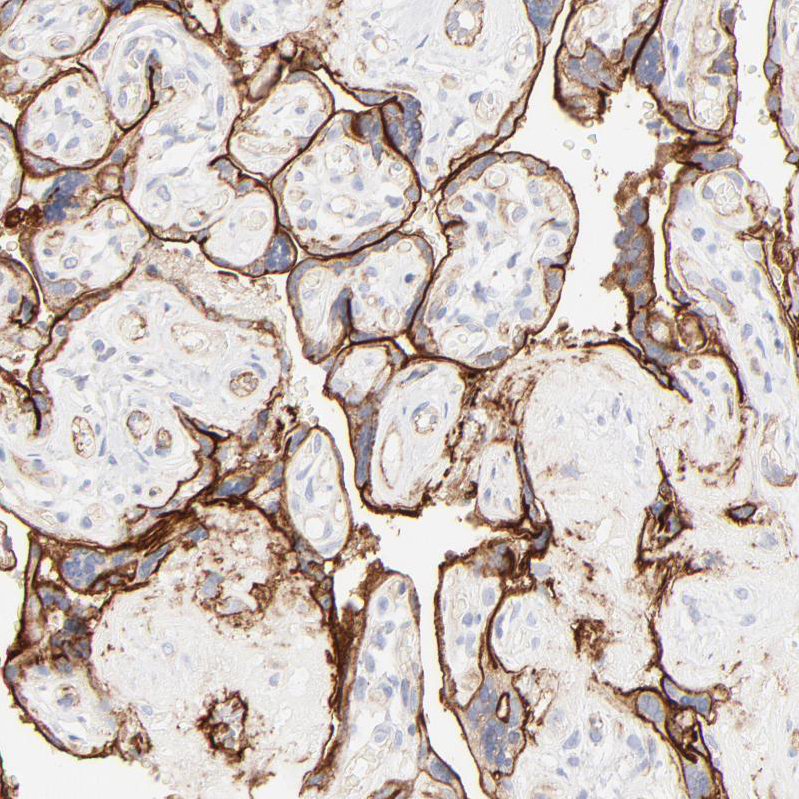

Immunohistochemistry analysis in human placenta and skeletal muscle tissues using HPA002642 antibody. Corresponding ITGA5 RNA-seq data are presented for the same tissues.